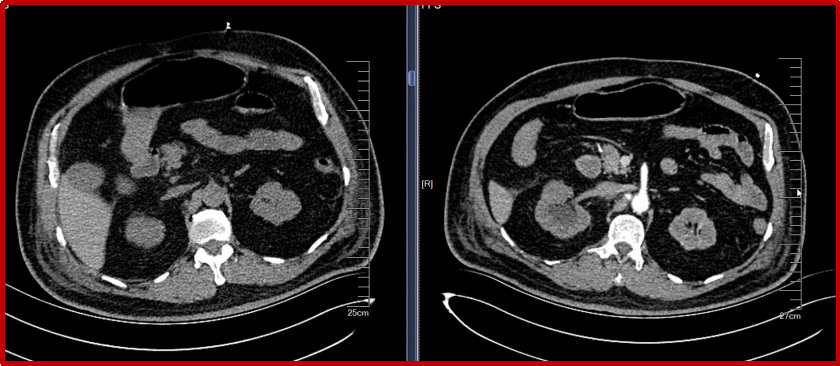

认真读术前影像:增强CT和内镜(尤其是急诊内镜)对明确出血部位至关重要,可指导有的放矢的介入治疗。

图:增强CT造影剂外溢

图:A:动脉期十二指肠球部、降段见结节状及线状高密度影;B:静脉期十二指肠内高密度影增多,强化程度稍减低。